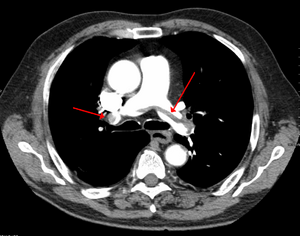

Chest spiral CT scan with radiocontrast agent showing multiple filling defects both at the bifurcation ("saddle" pulmonary embolism) and in the pulmonary arteries.

التصوير الطبقي المحوسب

التصوير الطبقي المحوسب للرئة والمصحوب باستخدام الصبغة المشعة في الوريد أصبح واسع الانتشار والاستخدام في تشخيص المرضى المشتبه بإصابتهم بالانصمام الرئوي، لهذا النوع من التصوير حساسية تبلغ 83% ودقة نوعية تصل إلى 96%.[24].[25]